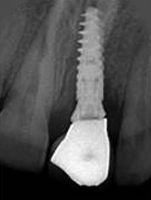

X-ray of Implant

Single Tooth Implant

X-ray of Implant + Abutment

X-ray of Implant +

Abutment + Prosthesis